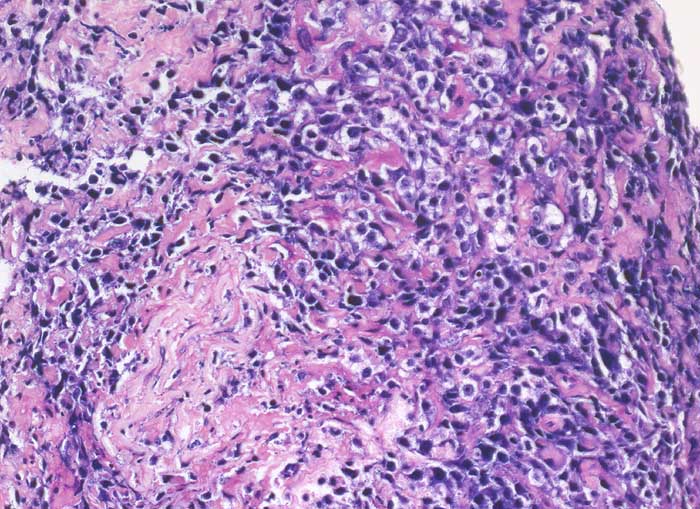

PathoPic – image database / PathoPic ID 6393 - diffuses grosszelliges B-Zelllymphom

diffuses grosszelliges B-Zelllymphom

Nierenbecken

Nierenhilusweichteile: diffuse Infiltrate atypischer lymphoider Zellelemente mit klarem Zytoplasmasaum.

Immunphänotypisch sind die Tumorzellen positiv für den Pan-B-Zell-Marker CD20 und fokal positiv für CD10. Daneben reaktive CD3 und CD5 positive T-Zellen. Negativ sind Antikörper gegen Zytokeratine sowie gegen Nierenzell-assoziierte Antigene. Die Prolfierationsrate ist hoch, stellenweise über 80%.

Nieren-Tumor rechts. DD: Urothel-Ca.